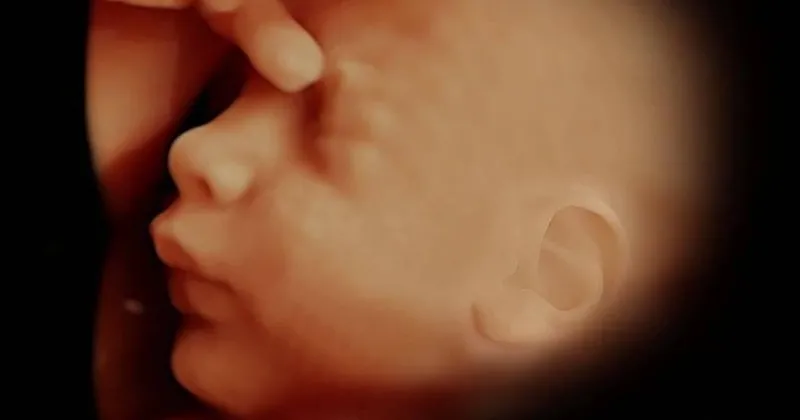

Dört boyutlu ultrason sgk lılara 300 tl i̇kinci düzey ultrason sgk lılara 300 tl i̇leri düzey ultrason sgk lılara 300 tl. Fetal tıp alanında uzmanlaşmış deneyimli hekimler tarafından ileri teknoloji ürünü olan yüksek rezolüsyonlu 4d ultrasonografi cihazı ile daha sağlıklı ve daha kaliteli bir şekilde yapılabilmektedir. Daha iyi görüntü için bebeğin çevresindeki su miktarı boldur. Tatmin edici kalitede görüntü talep eden bayanlar için ayrıca video ve cd olarak da artık verilebilmektedir.